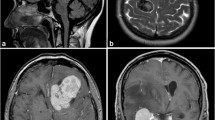

Using the above described approach, 565 patients (406 females, 72%; 159 males, 28%; median age 59 years, range: 7–91 years) with available preoperative MRI who underwent surgery between 1991 and 2018 were identified and included into subsequent analyses (Fig. 2). Data about adjuvant irradiation was available in 550 patients (97%); among those, adjuvant irradiation was administered in 42 cases (8%). Clinical, histopathological, and radiological data are summarized in Table 1. In univariate analyses, numerous correlations between the analyzed imaging variables were detected (suppl. table).

Although providing extensive analyses in a large series of meningioma patients, the authors are aware of some limitations of the study. Aside from the retrospective character of the series with the typical, attributed risks such as selection bias, preoperative MRI was only available in a subset of the entire patient cohort (Fig. 1) but was mostly lacking in cases being operated in the early years of the inclusion period. In fact, this might have significantly impacted follow-up, which was considerably shorter in the current patient collective than from the entire database (26 months vs 41 months, data not shown). The lack of correlation between the dichotomized extent of resection and recurrence in the entire cohort is remarkable. As subgroup analyses of patients with long-term follow-up confirmed STR as a strong risk factor for recurrence, this observation might be caused by the limited observation period of the entire study population. MRI was performed in our hospital and by a number of outpatient radiologists and other hospitals; thus, imaging quality and techniques differed widely, and technical specifications, e.g., the field strength or manufacturer, cannot be provided. Exact data about adjuvant irradiation was rarely available and was therefore not considered in further statistical calculations. Although calculated using an established formula, precision of volume quantification (especially of edemas, which might display non-spheroid spread along the white matter) is limited. On the other hand, 3D-volumetry/segmentation could not be provided due to technical reasons. An internal or external validation of the parameters on MRI has not been provided, yet. Thus, we are aware of a potential interrater variability due to subjective evaluation of the radiological variables, and therefore, an external validation is being planned in the future. Finally, data from molecular analyses and proliferation index were only available in selected patients and were therefore not considered.